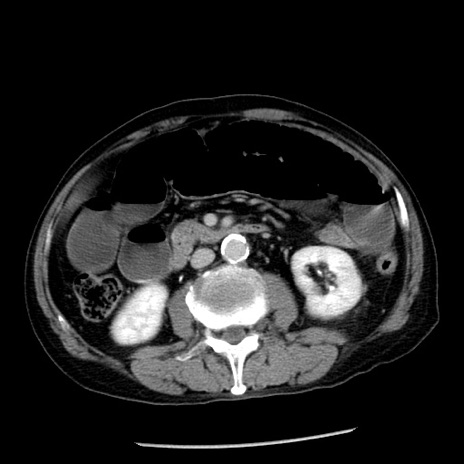

症例26(横断像)

【症例】80歳代男性

【主訴】嘔吐

【現病歴】昨晩2回嘔吐あり、今朝になっても嘔吐あり。来院。

【既往歴】胃潰瘍

【身体所見】意識清明、BT 37.6℃、BP 166/95mmHg、HR 100bpm、SpO2 97%、腹部:平坦・軟、腸蠕動音聴取良好、圧痛なし。

【データ】WBC 21900、CRP 1.46